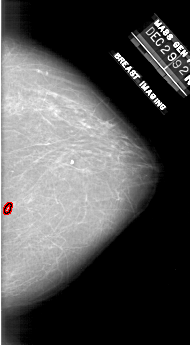

A_1910_1.LEFT_MLO

LEFT_MLO LINES 6466 PIXELS_PER_LINE 4006 BITS_PER_PIXEL 12 RESOLUTION 43.5 NON_OVERLAY

FILE: A_1910_1.RIGHT_MLO.OVERLAY

TOTAL_ABNORMALITIES 1

ABNORMALITY 1

LESION_TYPE CALCIFICATION TYPE PLEOMORPHIC DISTRIBUTION CLUSTERED

ASSESSMENT 4

SUBTLETY 3

PATHOLOGY BENIGN

TOTAL_OUTLINES 1

BOUNDARY